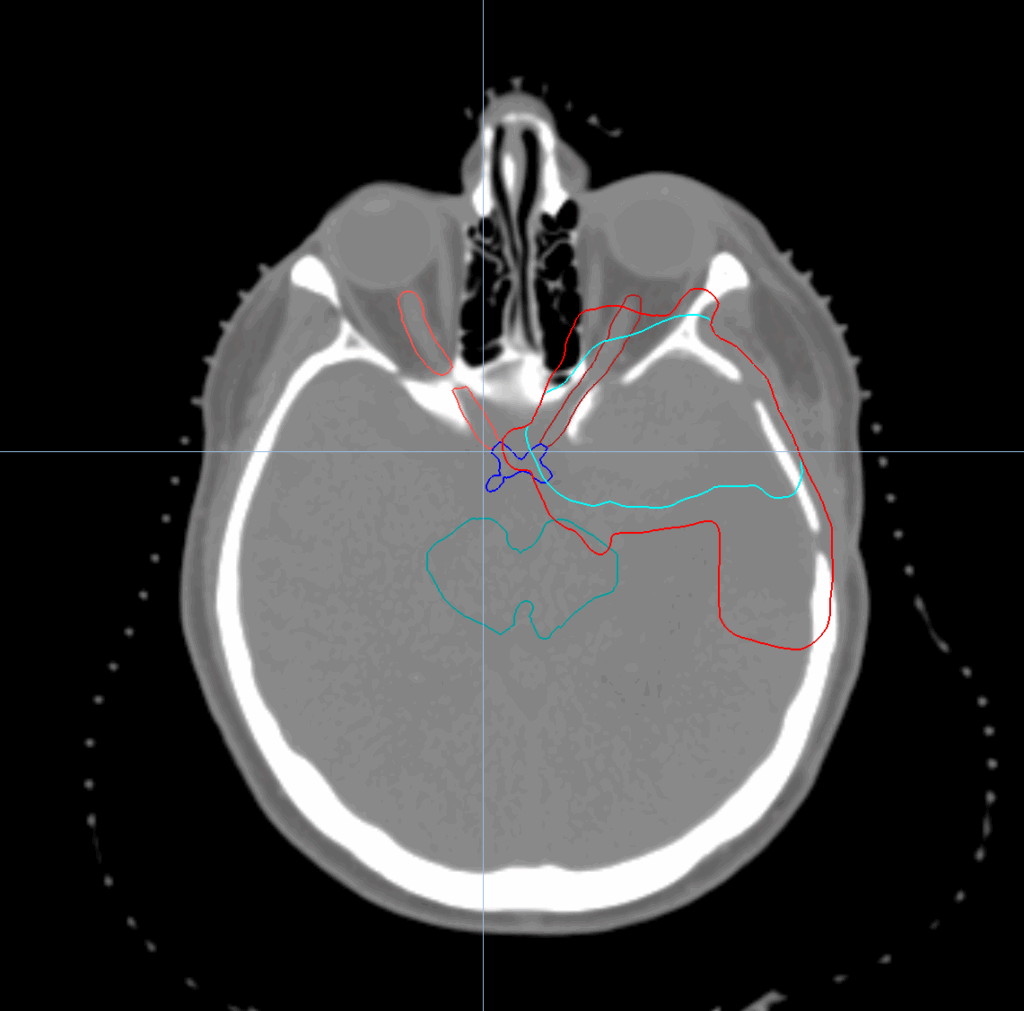

Meningioma

< View All Plan Studies RADIXACT SYSTEM Meningioma Case History AGE: 76-year-oldGENDER: Male Medical History Immidiate tolerance: Grade II dermatitis with eyelid edema, Grade I conjunctivitis resolved with Sterdex Diagnosis: Squamous cell carcinoma of the right lower eyelid Planning CT Images Treatment Plan Images ClearRT® Images Treatment Planning Highlights Fractionation / Protocol Used 70.20 Gy […]